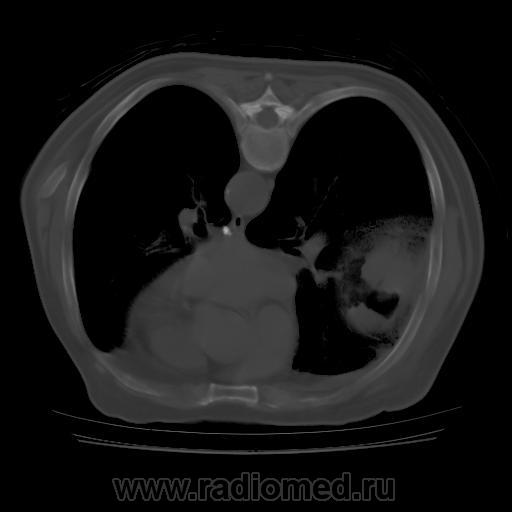

Правое легкое: в проекции средней доли (S3,4,5) определяется объемное образование преимущественно однородной структуры с ровными, четкми контурами размерами 92х88х94мм. Плотность его составляет 19-25 едН. В медиальных отделах образования содержится серповидная полоска воздуха. Латеральные отделы образования выходят за контуры грудной полости на 42 мм. На этом участке ребра не дифференцируются. Внутренний контур передней зубчатой, подлопаточной мышц размытый, граница между образованием и ними отчетливо не видна. Кзади от образования, в кортикальных отделах в легочной ткани инфильтрация. Кпереди от описанного образования расположен участок, широким основанием прилежащий к грудной стенке, имеющий плотность 12-20 ед.Н, однородную структуру, размеры 14х48мм. Прилежащее ребро интактно.

Наблюдение на самом деле весьма редкое и интересное. Для начала; это не эхинококк и конечно не мезотелиома. Данные заболевания не дают такую скиалогическую КТ картину: полость с содержимым, серпом воздухом и с деструкцией рёбер, лопатки и инвазией грудной стенки. Такой агрессивный характер инфекции может быт при актиномикозе; но при нём идёт диффузный процесс; не характерно образование таких больших полостей с внутренними включениями.

Аспергиллус может расти инвазивно и вызывать деструкцию в костях; есть отдельная форма: инвазивный аспергиллёз... Я прикрепил ниже сканы аспергиллёза с инвазией основания черепа. Но для неё не характерно образование полостей с "грибковым шаром"... Это признак мицетемы (отдельная форма аспергиллёза). Если поразмыслить логически; должен быть субстрат; а потом уже "сел" гриб. Я думаю дело было так; у пациента есть в наличии мелкоклеточный рак лёгкого или туберкулёзная полость; а потом присоединился аспергиллус и мы получили представленную картину. По другому никак не укладывается. ИМХО.